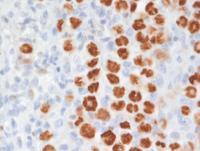

Immunostains in GZL

Immunostains show that the large cells are uniformly positive for CD20, and Oct-2. Additional B-cell markers including CD79a, Pax5 (not shown) were also positive indicative of a well preserved B-cell program. The backgound is rich in CD3+ T-cells. There was also weak CD5 expression in the large cells (not shown). Rare large cells express weak CD30 but there is strong uniform CD15 with weak variable Mum1 (usually strong in pure cHL).

Notably, most of the lymphoma cells are moderately positive for PD-L1.

GZL-CD20-IHC

GZL-Oct2-IHC